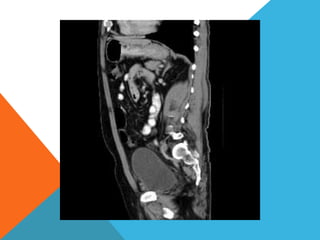

El paciente presentó síntomas de sangrado digestivo y pérdida de peso. Exámenes revelaron gastritis crónica asociada a H. pylori. Un tumor fue descubierto en una colonoscopia normal. La cirugía removió un tumor fibroide solitario, una rara neoplasia mesenquimal que usualmente crece lento y tiene bajo potencial de malignidad. El pronóstico después de la remoción quirúrgica es generalmente bueno.